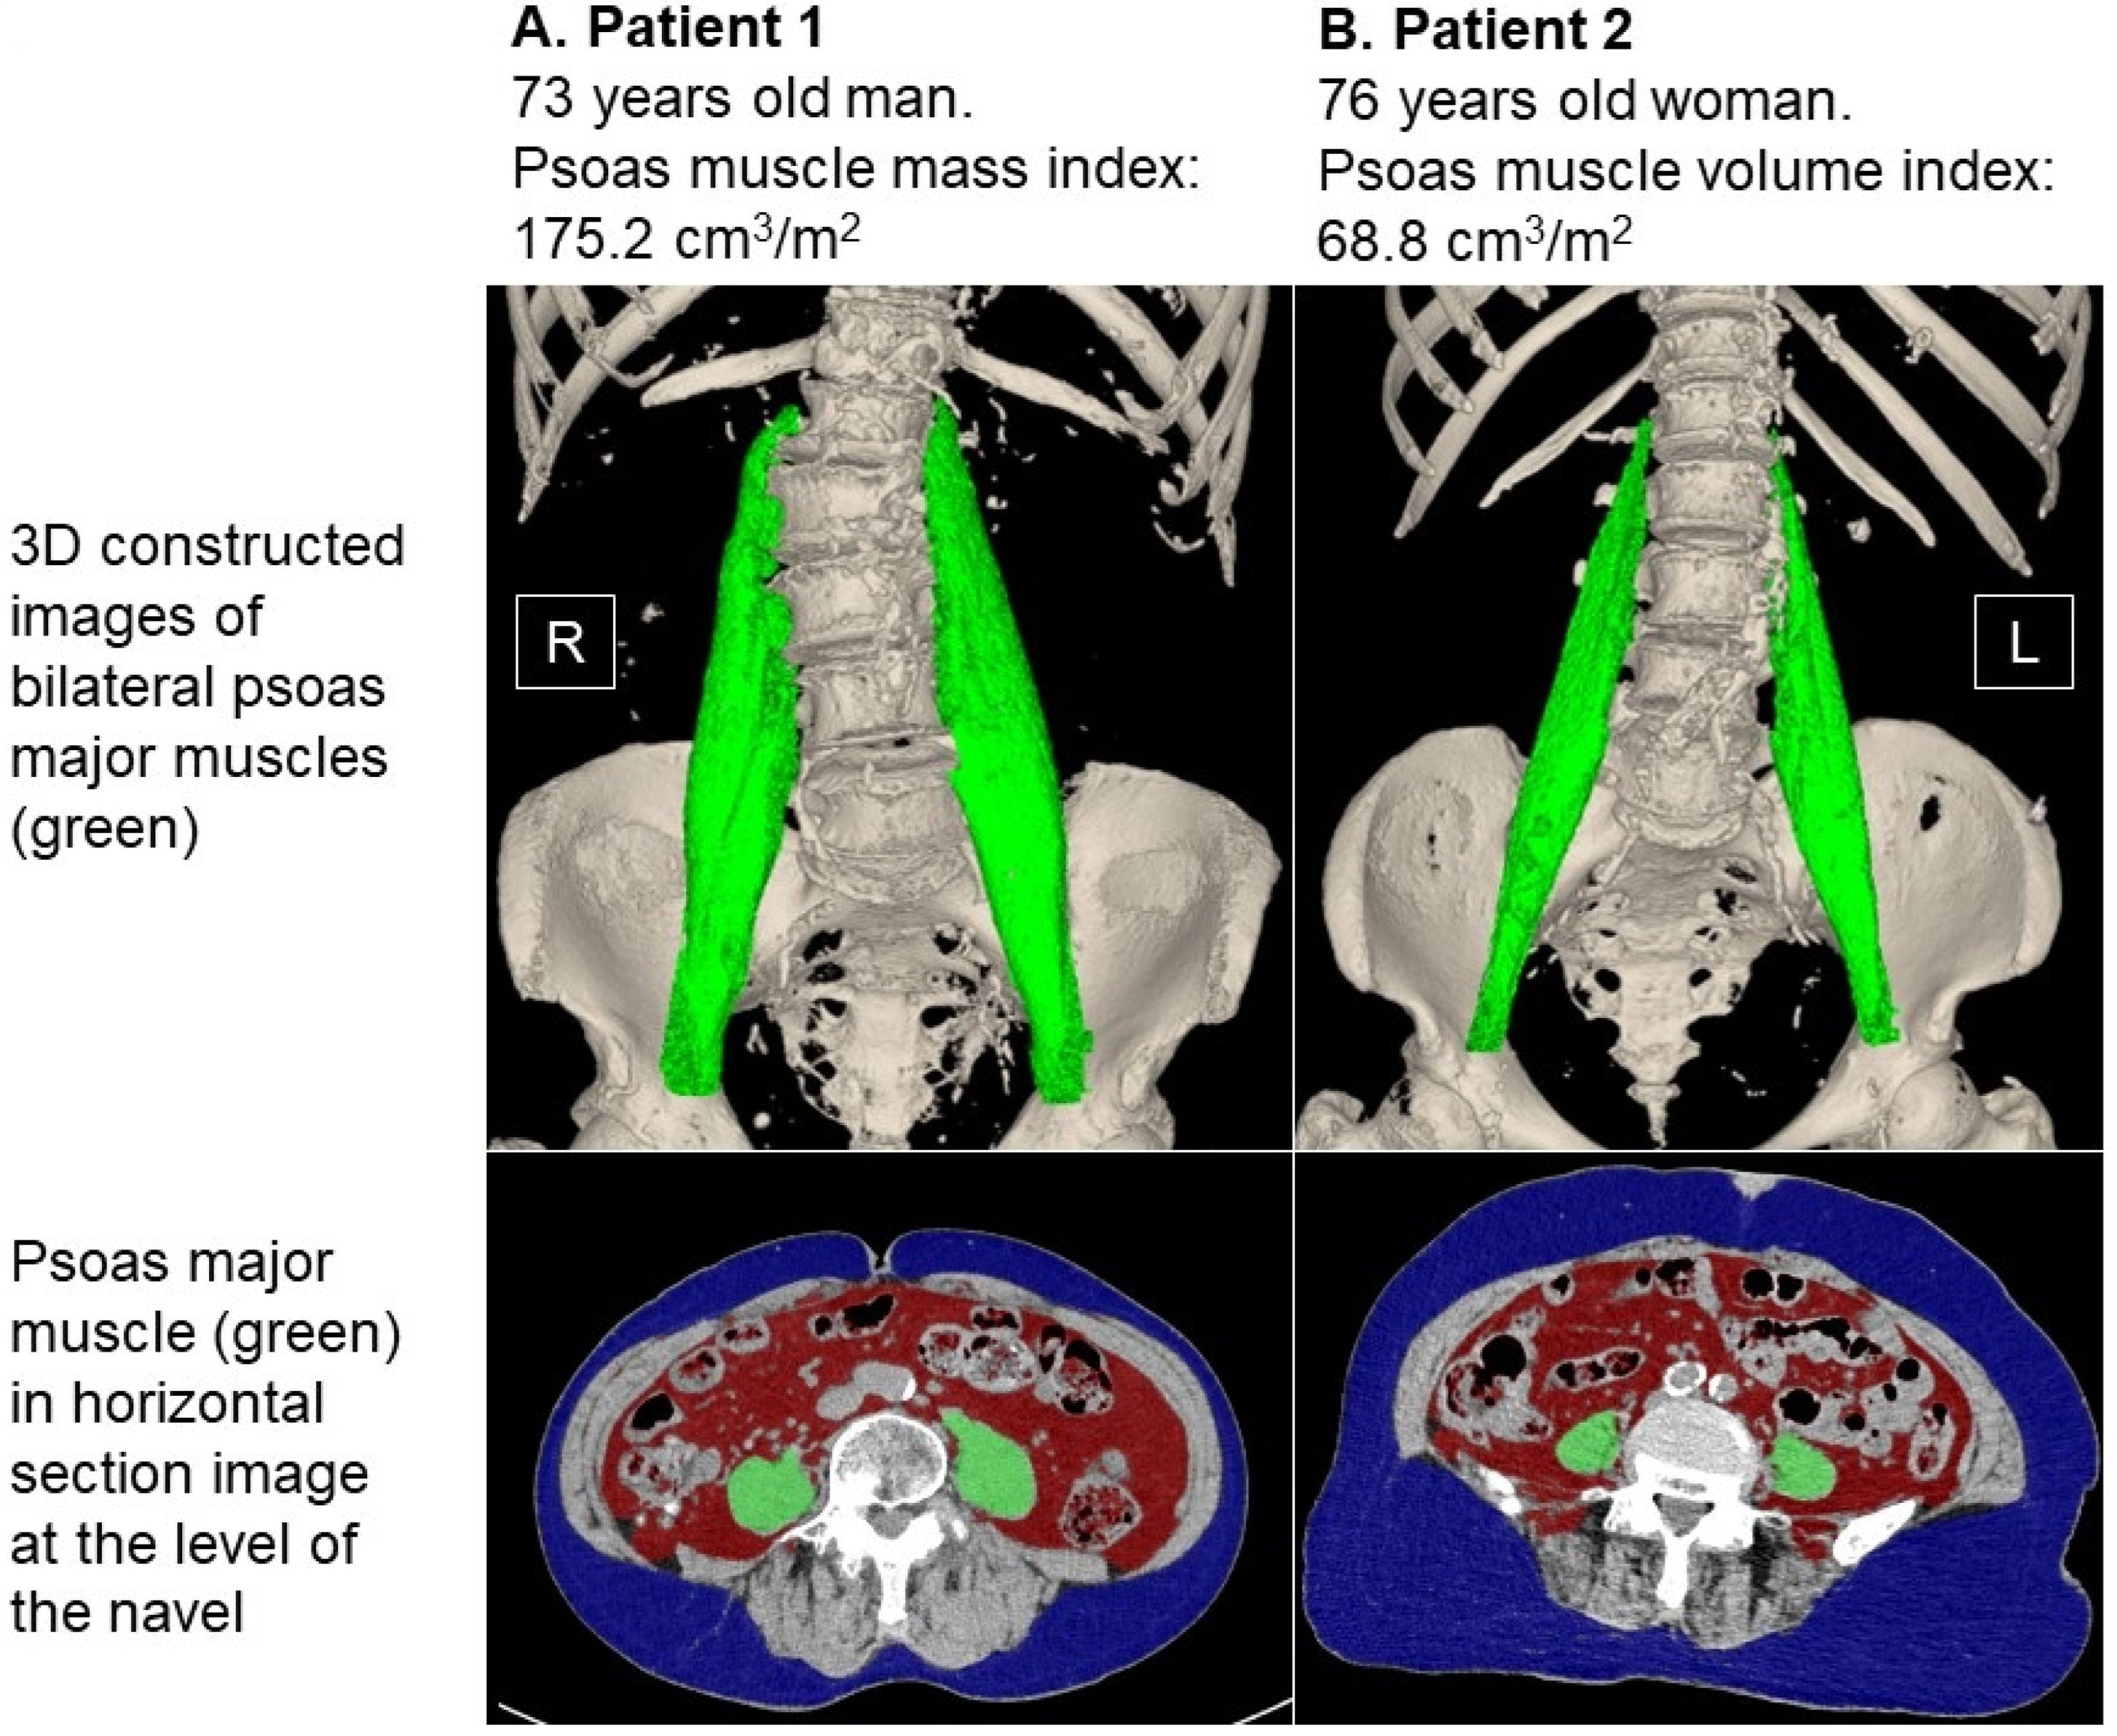

2.2. Measurement of Psoas Muscle Mass